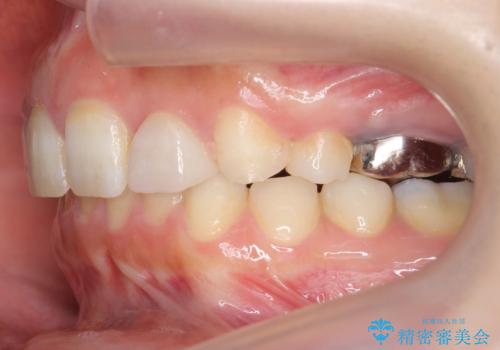

出っ歯を治したい 過蓋咬合

- 出っ歯を主訴に来院。

かみ合わせが深く、治療に時間がかかりました。

上顎2番は矮小歯だったのをセラミックで被せています。

口唇の突出感がなくなり、理想的な横顔になりました。